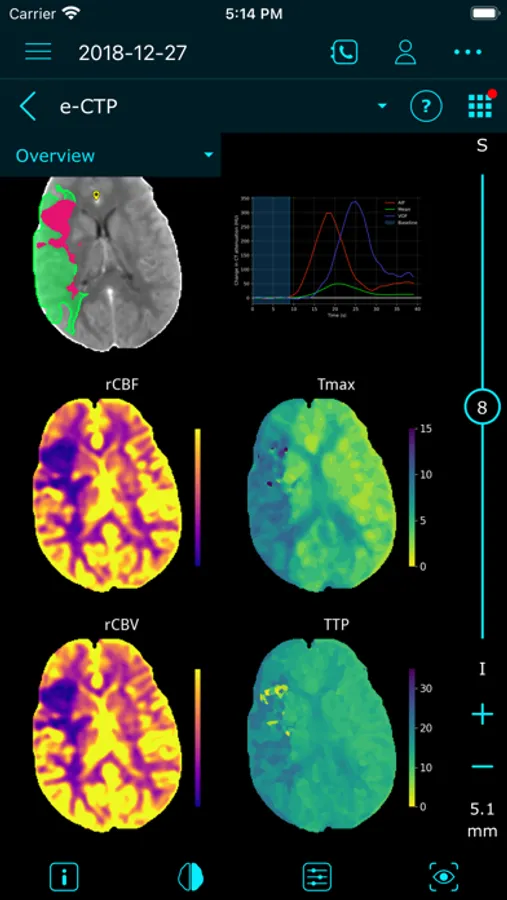

e-Stroke consists of three modules (e-ASPECTS*, e-CTA*, and e-CTP*), supporting the full range of stroke imaging needs, from simple NCCT scans, to more advanced CT Perfusion assessments.